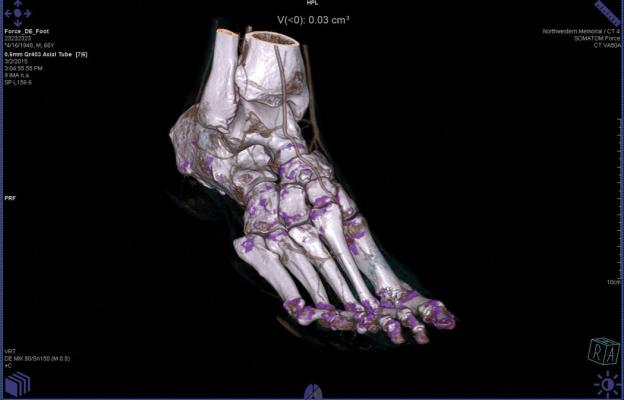

Gout in the foot detected with the Somatom Force CT system’s dual energy, which could have otherwise been missed.

Dual energy scans can also prove useful in diagnosing gout in an acute care setting. Pain in the afflicted joint could be a symptom of any number of conditions, but if gout is suspected, spectral CT can be used to reveal deposits of monosodium urate crystals (MSU) around the joint. “In an environment where you may not have a full history on the patient ... the ED physician is faced with so many choices,” Mochon explained. “Dual energy can quickly direct them to the answer.”